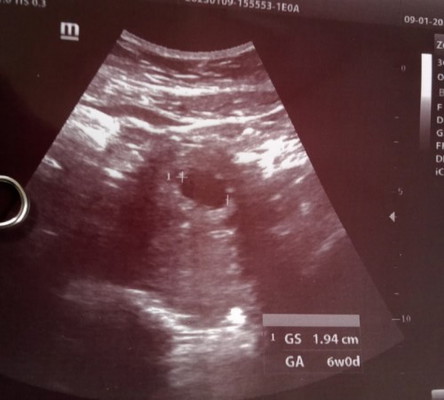

อยากได้เขามากขออย่าให้เป้นท้องลมเลยนะพูดไม่ออกเลยค่ะคุณหมอยังไม่เสียงหัวใจของเด็กยังไม่เห็นอะไรเลย😭

กี่วีคแล้วคะแม่ ถ้าครรภ์ยังอ่อนต้องใจเย็นๆนะคะ น้องอาจจะตัวเล็ก หรือเจริญเติบโตช้า บางคนเพิ่งเจอน้อง7-10วีคก็มีค่ะ หรืออาจจะมากกว่านี้ แม่ต้องใจเย็นๆพยายามอย่าคิดมากนะคะ ขอให้สมหวังค่ะ♥️

อายุครรภ์น้อยต้องซาวทางช่องคลอดถึงจะเห็นชัดค่ะ แม่ซาวช่องคลอดไหมคะ

เราก็ยึดจากใบซาวค่ะแม่ เพราะท้องต่อจากคนพี่โดยที่ประจำเดือนยังไม่มาเลย(คนพี่1.1ปีให้นมอยู่)